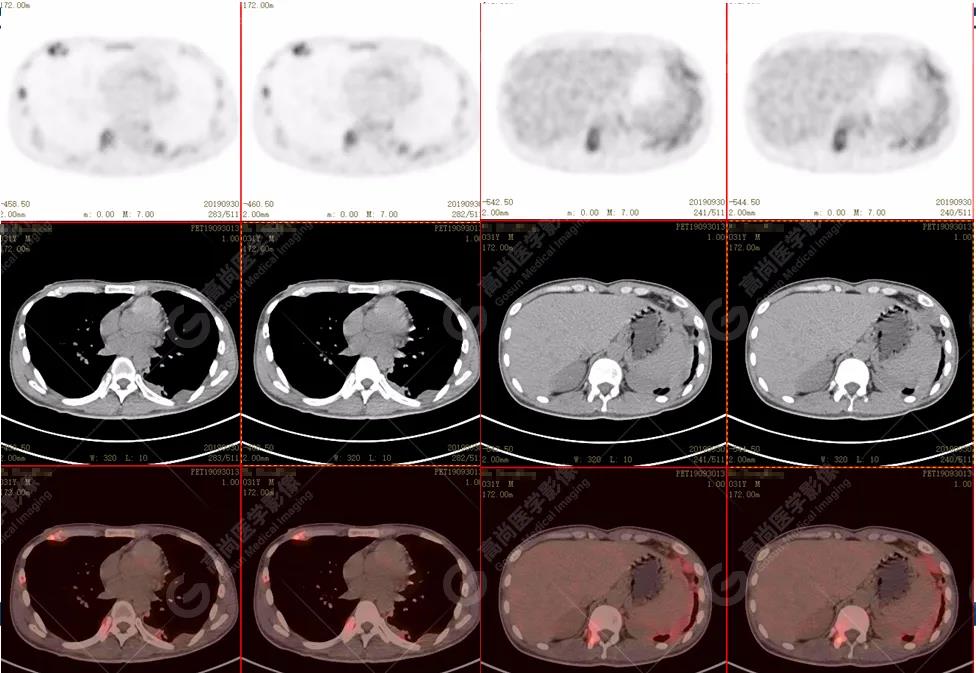

PET/CT全身圖

脊柱多發(fā)椎體及附件骨質(zhì)破壞,代謝不均性增高

全身多處骨質(zhì)破壞,代謝不均性增高

全身多發(fā)高代謝腫大淋巴結(jié),中央代謝缺損

左肺上葉尖后段及下葉背段多發(fā)簇狀斑點(diǎn)狀高代謝灶

左側(cè)胸膜結(jié)節(jié)樣增厚,代謝不同程度增高

雙肺、左側(cè)胸膜多發(fā)結(jié)節(jié)影,全身多處骨質(zhì)破壞,全身多發(fā)淋巴結(jié)腫大,代謝攝取不均勻性增高。